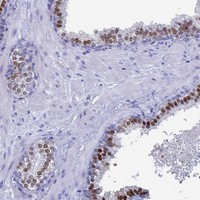

- Immunohistochemical staining of human prostate with TMEM244 polyclonal antibody (Cat # PAB24398) shows strong nuclear positivity in glandular cells at 1:50-1:200 dilution.

- Immunohistochemistry (Formalin/PFA-fixed paraffin-embedded sections)